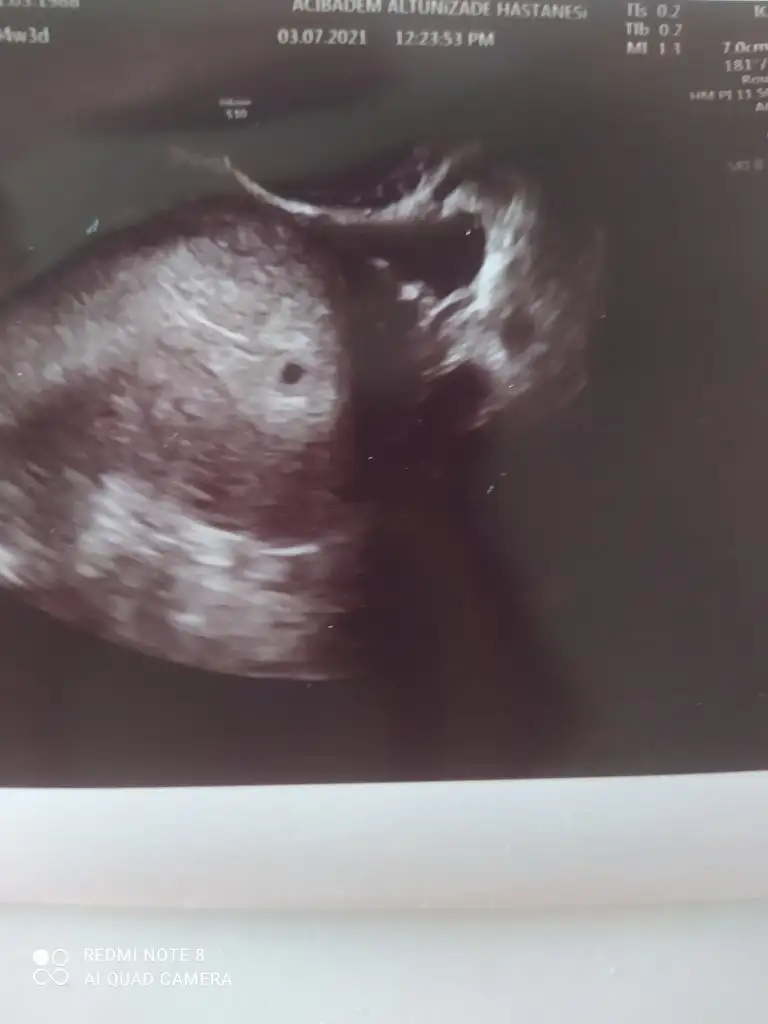

Gurubun ilk kese resmi. Şuana kadar kese resmi atan hiç olmamistiEvet gördüm çok şükür minik bir kese.sizde hayırlısıyla kesin görürsünüz

Bir de 5+5'te sadece kese mi görüntü kalp atışı için doktor bir şey dedi mi size?

Kese ve bebek gözüktü kalp atışı için cumartesi gidicem bir aksilik olmazsa 6+3 olcak o gün